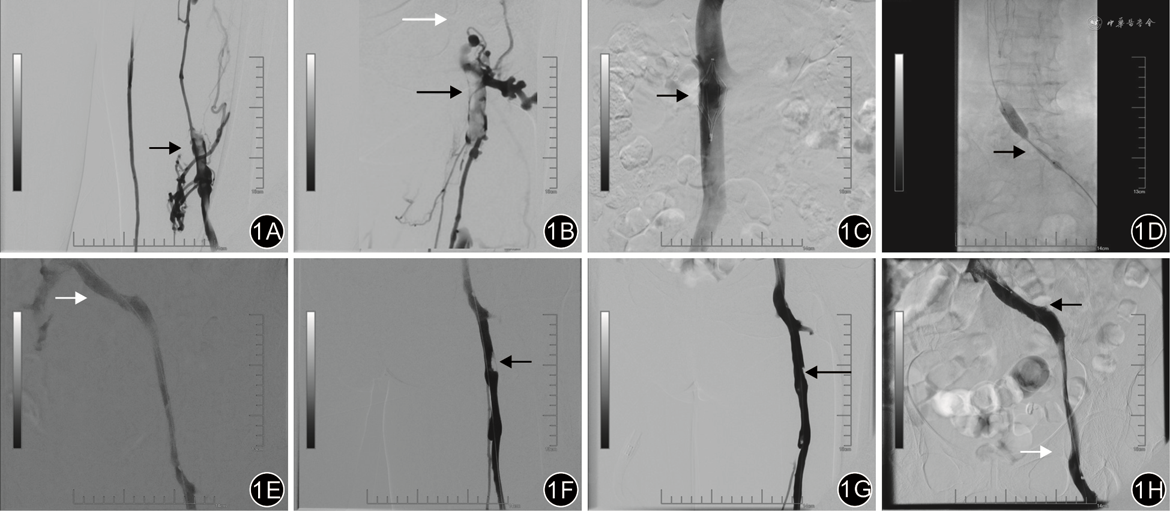

68例患者术后均获随访,随访时间12~24(17.3±3.5)个月。同期组患者术后1、6、12、24个月支架累积通畅率分别为97.1%、94.3%、94.3%、94.3%,分期组分别为97%、93.9%、93.9%、93.9%。患者术后肢体肿胀程度均较术前明显改善。术后12个月时,2组患者的支架累积通畅率、肢体周径差、PTS发生率及VCSS评分差异均无统计学意义(P值均>0.05),见表2。典型病例见图1。